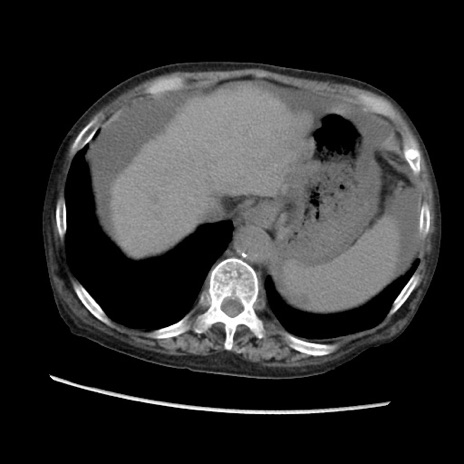

症例31(横断像)

【症例】80歳代 女性

【主訴】腹部膨満感

【現病歴】他院にて肝硬変にてフォロー中。1週間前から便秘、腹部膨満感、臍部腫瘤あり受診となる。

【既往歴】肝硬変

【身体所見】腹部膨隆あり、皮膚変化なし、疼痛なし。

【データ】WBC 4600、CRP 0.25